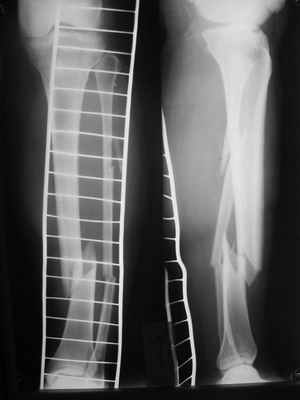

Здравствуйте уважаемые коллеги. Позвольте поделиться опытом применения интрамедуллярного остеосинтеза большеберцовой кости имплантатами компании ?Остеомед" с запатентованной прицельно-навигационной системой для дистального блокирования ?Интерлок". Для определения длинны и диаметра стержня использовали линейку-шаблон, позволяющей с легкостью рассчитать длину и диаметр стержня с проекцинно искаженными размерами, как конечности, так и линейки-шаблона.Дистракцию производили с помощью спицевого дистрактора с последующей закрытой репозицией отломков винтами Шанца. Все основные этапы производили по методике АО, гарантированное дистальное блокирование достигается за счет центрирования отверстий, путем контролирования смещения стержня в костномозговом канале в сагиттальной плоскости. Клинический пример:Больная Я. 45 лет, пострадала в результате случайного падения на улице 19.12.2005., имеет место открытый 1 степени перелом обеих костей левой голени со смещением отломков.произведена закрытая репозиция перелома с последующим введением стержня (на данном этапе производился рентген-контроль)Убедившись в достаточной репозиции перелома, произведено дистальное и проксимальное блокирование интрамедуллярного стержня.Общее время затраченное на оперативное вмешательство составило 45 минут.

можно на фото взглянуть?